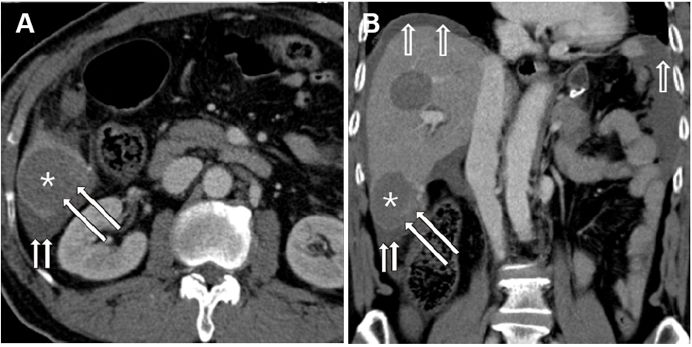

女性患者,42岁,因“上腹部疼痛伴间歇性呕吐半年”入院治疗。临床主要表现为急性胃流出道梗阻。血化验提示患者有贫血;胃镜提示胃窦幽门区前壁粘膜下肿物,通过幽门进入十二指肠,肿物表面粘膜有溃疡;腹部CT提示肿物8×7×4cm大小,胃窦起源进入十二指肠至水平部,不均一强化。患者接受剖腹探查,胃肿物局部切除术。术后恢复顺利。(手术标本见图)

图示 GIST切除标本 肿块顶点(红色箭头), 肿物基底 (绿色箭头),部分胃壁 (黄色箭头)